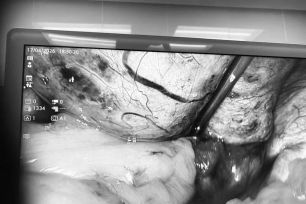

Cần Thơ: Khai trương phòng khám áp dụng công nghệ hiện đại

Ngày 8-12, tại TP Cần Thơ, Phòng khám Đa khoa Rebalance chính thức khai trương và đi vào hoạt động.